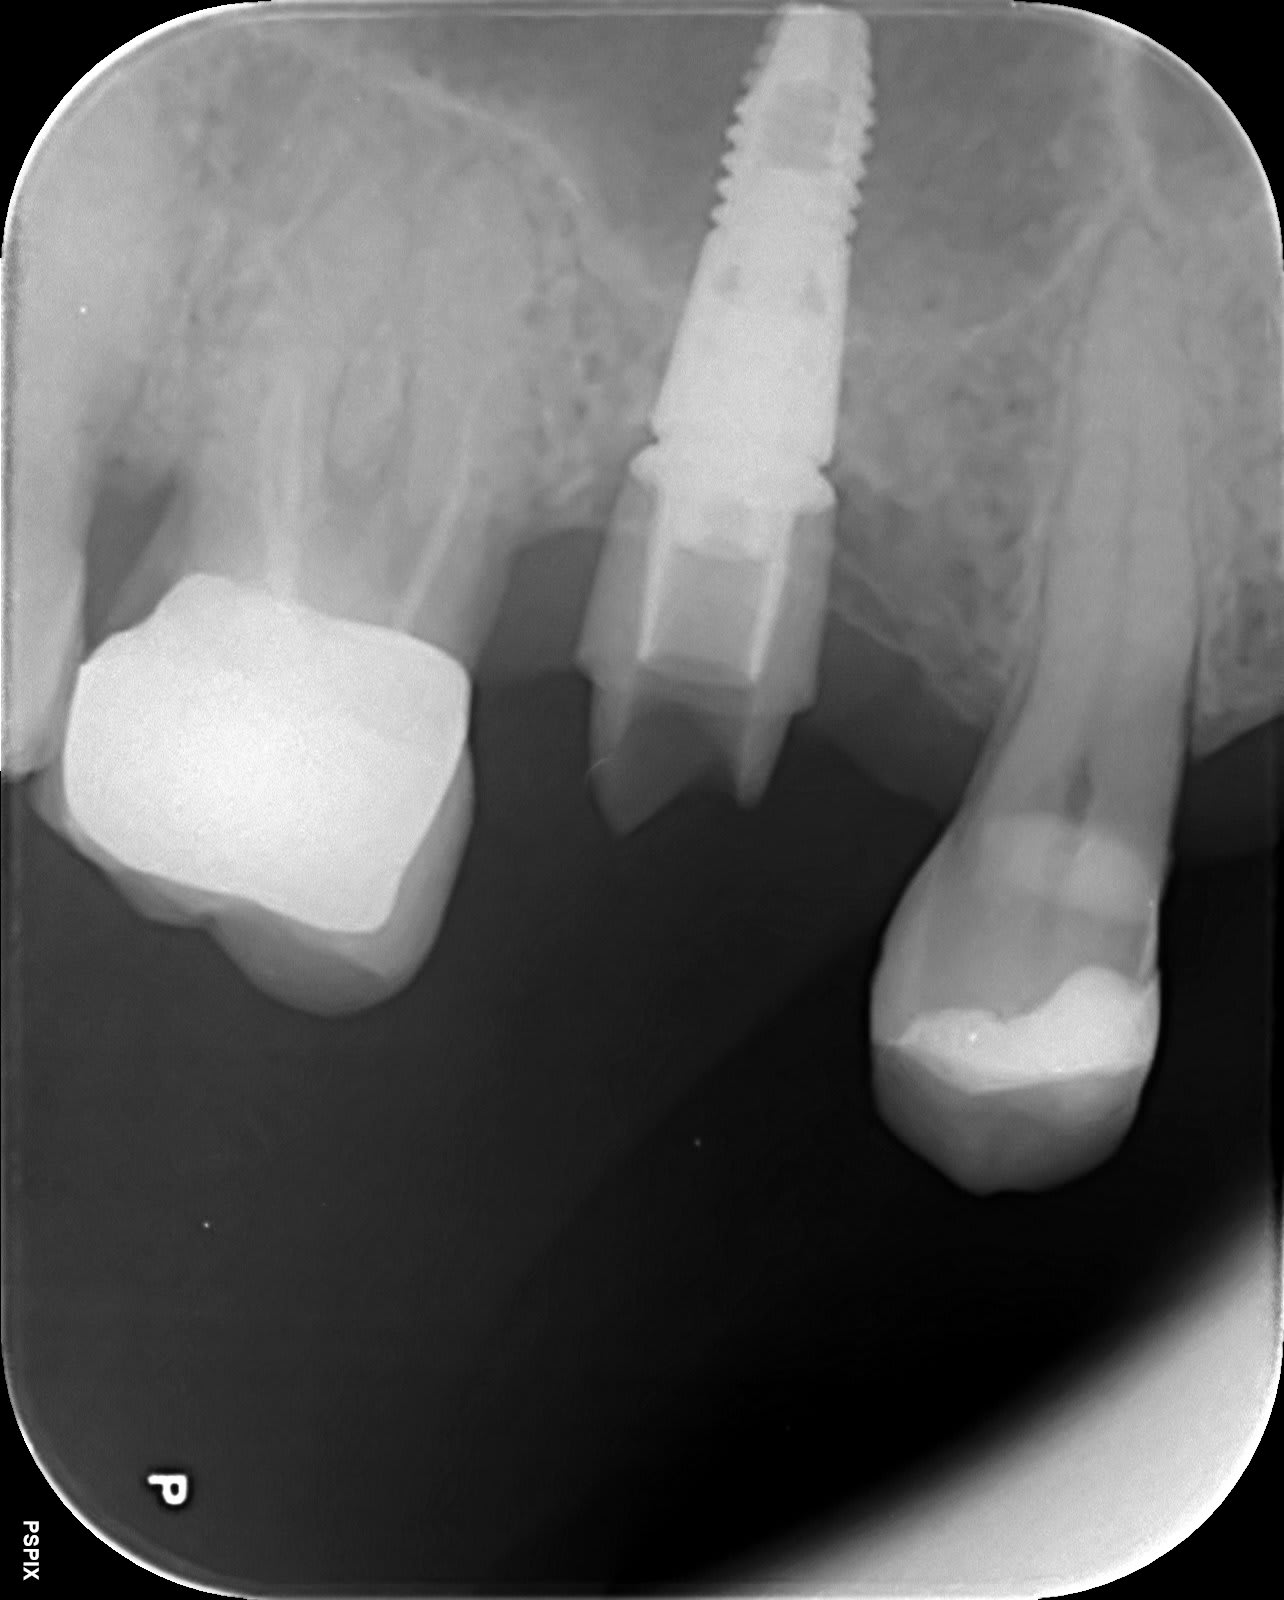

Identification implant

je pense a un astra?

oui

YES